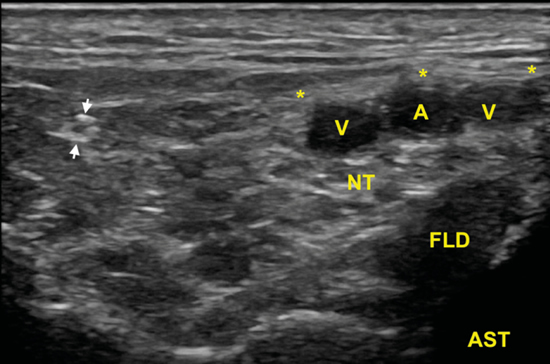

Se sitúa la sonda en el plano transverso (Figura 8) para localizar el nervio tibial en eje corto, y apreciar en un discreto desplazamiento distal como la rama calcánea se irá separando y distanciando en busca del aspecto posteromedial del calcáneo (Figura 9).

Figura 9. En esta imagen en eje corto, la rama calcánea (flechas) una vez que ha atravesado las láminas de la fascia crural (*) y se ha ido separando del nervio tibial (NT) que se encuentra debajo de los vasos (A, V), y sobre el tendón flexor largo del primer dedo (FLD) y el astrágalo (AST).